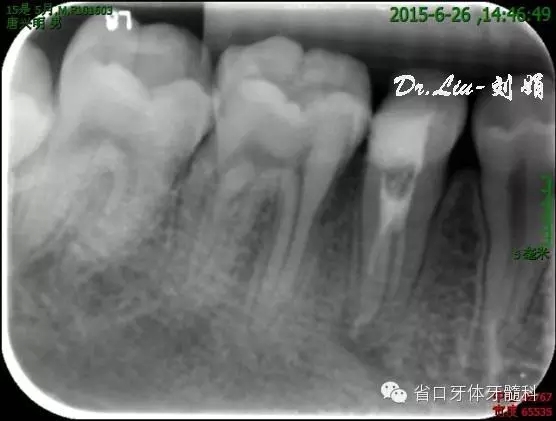

圖8:1月后復(fù)診根尖低密度影有消退趨勢

45橡皮障隔離下去封藥,清理根管,沖洗,紙尖干燥根管,拍攝試主尖片,顯微鏡下行熱牙膠根管充填,X線片顯示恰填。

圖10:根充后X線片